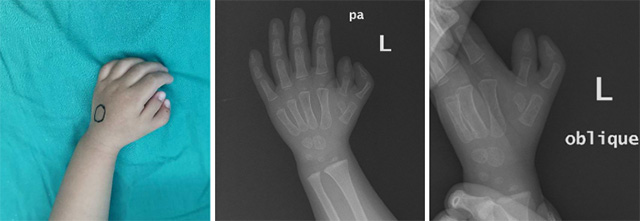

近期,玉溪市中醫(yī)醫(yī)院小兒骨科收治了兩名兒童蟹鉗樣復(fù)拇畸形的患兒。患兒分別為14個(gè)月大和20個(gè)月大,入院后小兒骨科針對(duì)患兒病情及時(shí)召開病歷討論專題會(huì),經(jīng)分析患兒相關(guān)查體及影象學(xué)檢查后考慮兩位患者分別為:先天性蟹鉗樣復(fù)拇畸形Wassel Ⅳ型和Ⅵ型 。

圖為患兒1的術(shù)前手外觀及影象學(xué)資料